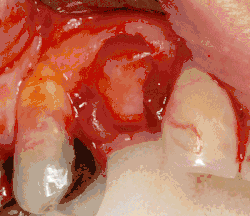

Через десну делается разрез, и лоскут ткани откидывается, чтобы показать кость челюсти.

Как только кость обнажена, серия упражнений создаёт и постепенно увеличивает участок (называемый остеотомией) для установки имплантата.

Крепление имплантата превращается в остеотомию. В идеале он полностью покрыт костью и не имеет движения внутри кости.

Если ширина кости недостаточна, она может быть выращена с использованием искусственных или кадеварных кусочков кости, чтобы выступать в качестве основы для роста естественной кости.

Когда требуется большее количество кости, её можно взять из другого места (обычно задней части нижней челюсти) и пересадить на участок имплантата.